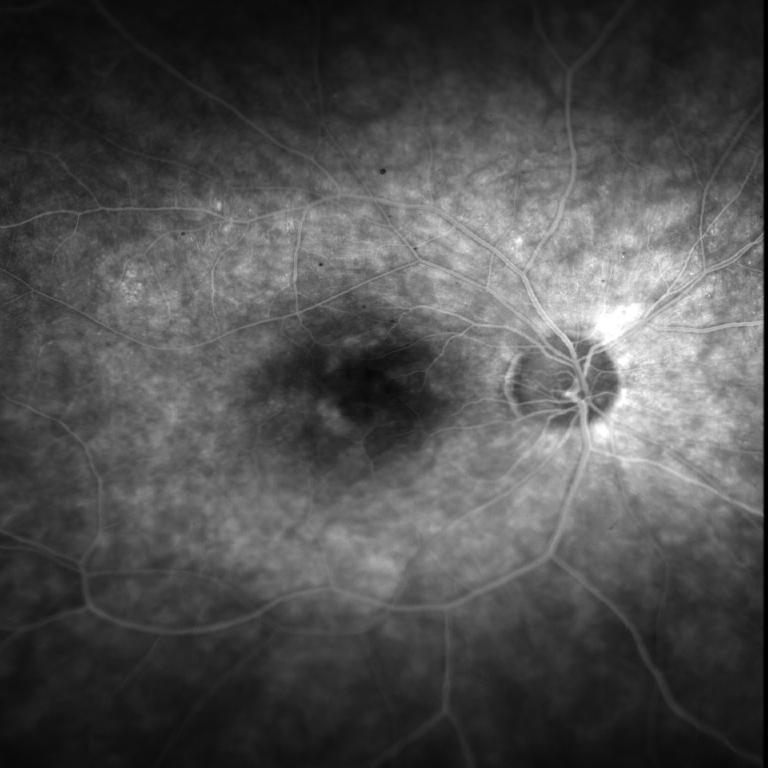

46 yo white female with family history of Autosomal Dominant Retinitis Pigmentosa with vision of 20/200 OU, who has been treated with numerous subtenon's kenalog injections and Diamox 500 PO BID and Nevanac TID without apparant response.